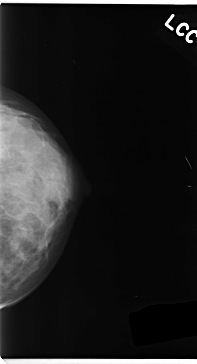

Digital Database for Screening Mammography

Volume: cancer_05 Case: C-0152-1

C_0152_1.LEFT_CC

LEFT_CC LINES 4720 PIXELS_PER_LINE 2552 BITS_PER_PIXEL 12 RESOLUTION 50 NON_OVERLAY

LEFT_MLO LINES 4704 PIXELS_PER_LINE 2552 BITS_PER_PIXEL 12 RESOLUTION 50 NON_OVERLAY